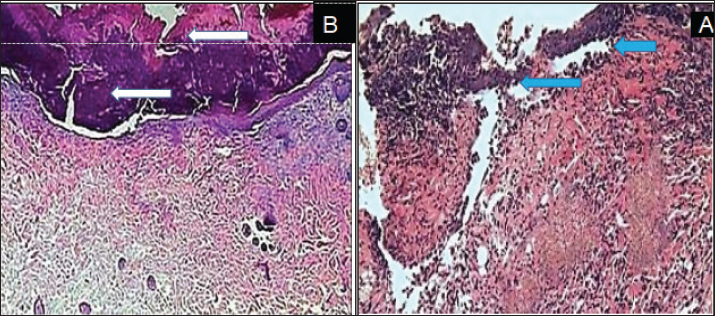

On day 7 Advanced epithelialization was observed on the inner wound margins in the SIS-ECM powder-treated group, with the epithelium beginning to cover the entire exposed wound edge (Fig. 3A). In contrast, the control group exhibited incomplete epithelization, with a persistent and notable infiltration of inflammatory cells (Fig. 3B).

Fig. 3. Histopathological section, at 7 days PO, (A) in control group showed neutrophils and mononuclear cells infiltration in the immature granulation tissue (Red arrow). (B) in treatment group, showed granulation tissue in the dermis with complete epidermal layer (Red arrow). (H& E stain 100X).

On 14 day epithelialization was complete in treated wounds, with the wound site densely filled by cohesive tissues and new collagen bundles (Fig. 4B). conversely, in control group displayed a persistence of delayed epithelial reorganization and fibrous tissue deposition (Fig. 4A). On day 35 Histological examination revealed near-complete recovery in the treated wound characterized by collagen reformation,skin keratinization, and the reappearance of hair follicles in the wound site (Fig. 5B). In contrast, the control wounds exhibited delayed healing, with advanced fibrosis and prominent scarring (Fig. 5A).

Fig. 4. Histopathological section, at 14 days PO, (A) in control group showed the reorganization of the collagen high and deposition of fibrous tissue (blue arrow). (B) in treatment group, showed thickened layer of epithelial cells extended over mature granulation tissue and under cellular debris (white arrow). (H and E X100).